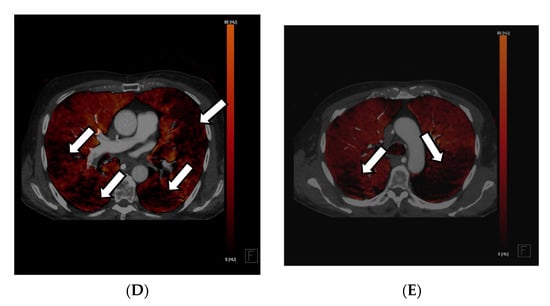

For diagnosing pulmonary embolism, iodine mapping, and perfusion analysis are advantageous features for the visualization of hypoperfused areas, usually V-shaped areas in the perfusion maps, which can be used as a colored overlay map on anatomic CT reconstructions according to Thieme et al., 2008 and many other publications. This semi-quantitative technique allows for relative measurements of iodine uptake in the lung parenchyma (See Figure 2A–D) [31,33,34,37,38,41].

Figure 2.

Application of iodine mappings and perfusion visualization facilitating DECT in a DSCT scan of a 23-year-old woman suffering from chest pain, tachycardia, and dyspnea. The 50 kV axial soft tissue kernel reconstruction CT angiography of the pulmonary arteries showed central thrombosis of both main pulmonary arteries on the right side (A,B) and the left side (C) with partial occlusion of the subsequent vessels. V-shaped perfusion deficits were reported in the perfusion maps (D,E), which can be correlated to segments 9/10. In correspondence to the missing contrast agent in the responding segmental arteries of these segments, a total occlusion was suspected. The patient was accordingly treated with systemic anticoagulation.

A potential limitation of angiographic imaging in the thorax is that, with first-generation DSCT, the 26 cm FOV may limit bone subtraction outside the central FOV. These limitations are significantly reduced by the 33 cm FOV of second-generation DSCT and, theoretically, are not an issue with single-source acquisition techniques [6].